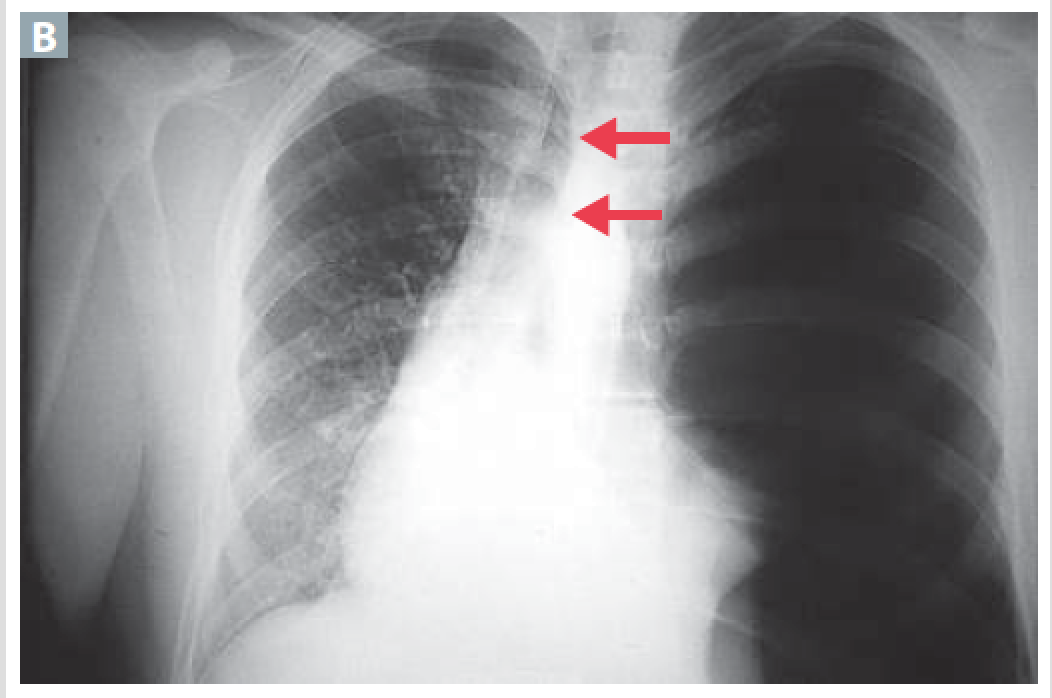

Headaches, dizziness, increased risk of aneurysm/ rupture of intracranial arteries from impaired blood drainage from the head (facial plethora)

Superior Vena cava syndrome